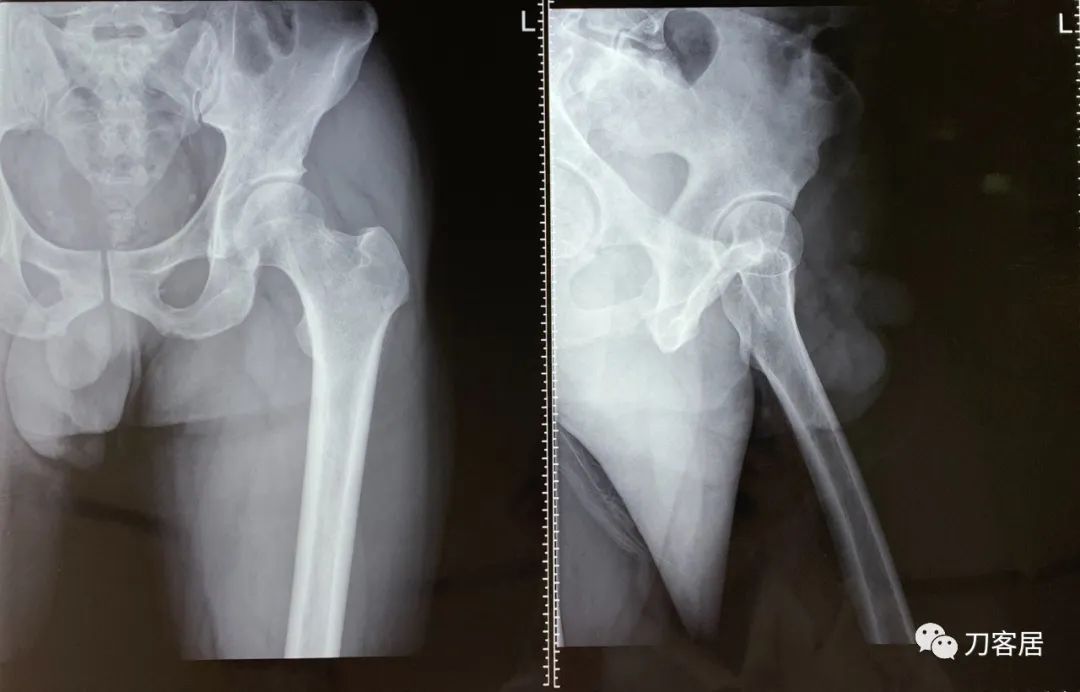

图2. 20220117宁夏医科大学总医院左髋关节正侧位X线片

图3. 20220117宁夏医科大学总医院左股骨正侧位X线片

当地医院接诊医生给患者拍左髋关节和左股骨正侧位X线片应该是为了排除左髋关节和左股骨是否存在问题。